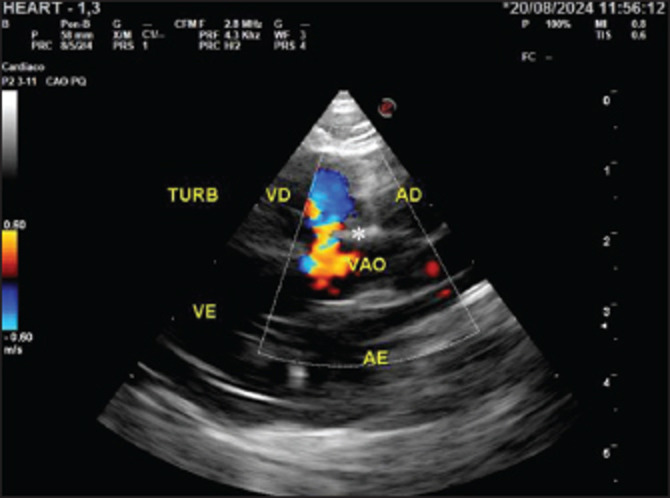

Case description: This article reports a case of PPH in association with a ventricular septal defect (VSD) in a pediatric canine patient. The dog, a female Shih Tzu, aged 2 months, presented with cyanosis, low weight, decreased body condition score (3/9), and underdevelopment in comparison with other puppies of the same litter. At physical examination, all parameters were within the normal range; however, there was a sound at the base of the heart during auscultation, and echocardiographic examination displayed VSD. Due to the dyspnea, thoracic radiography was performed, and the suspicion of PPH was confirmed. Peritoneopericardial hernioplasty surgery was indicated for a 2-month-old patient. During the surgical procedure, it was not necessary to enter the thoracic cavity in order to close the defect, and suture surgery was performed through the abdominal cavity accessed in the subxiphoidal region. Despite the high risks associated with the procedure, no intraoperative or anesthetic complications occurred.